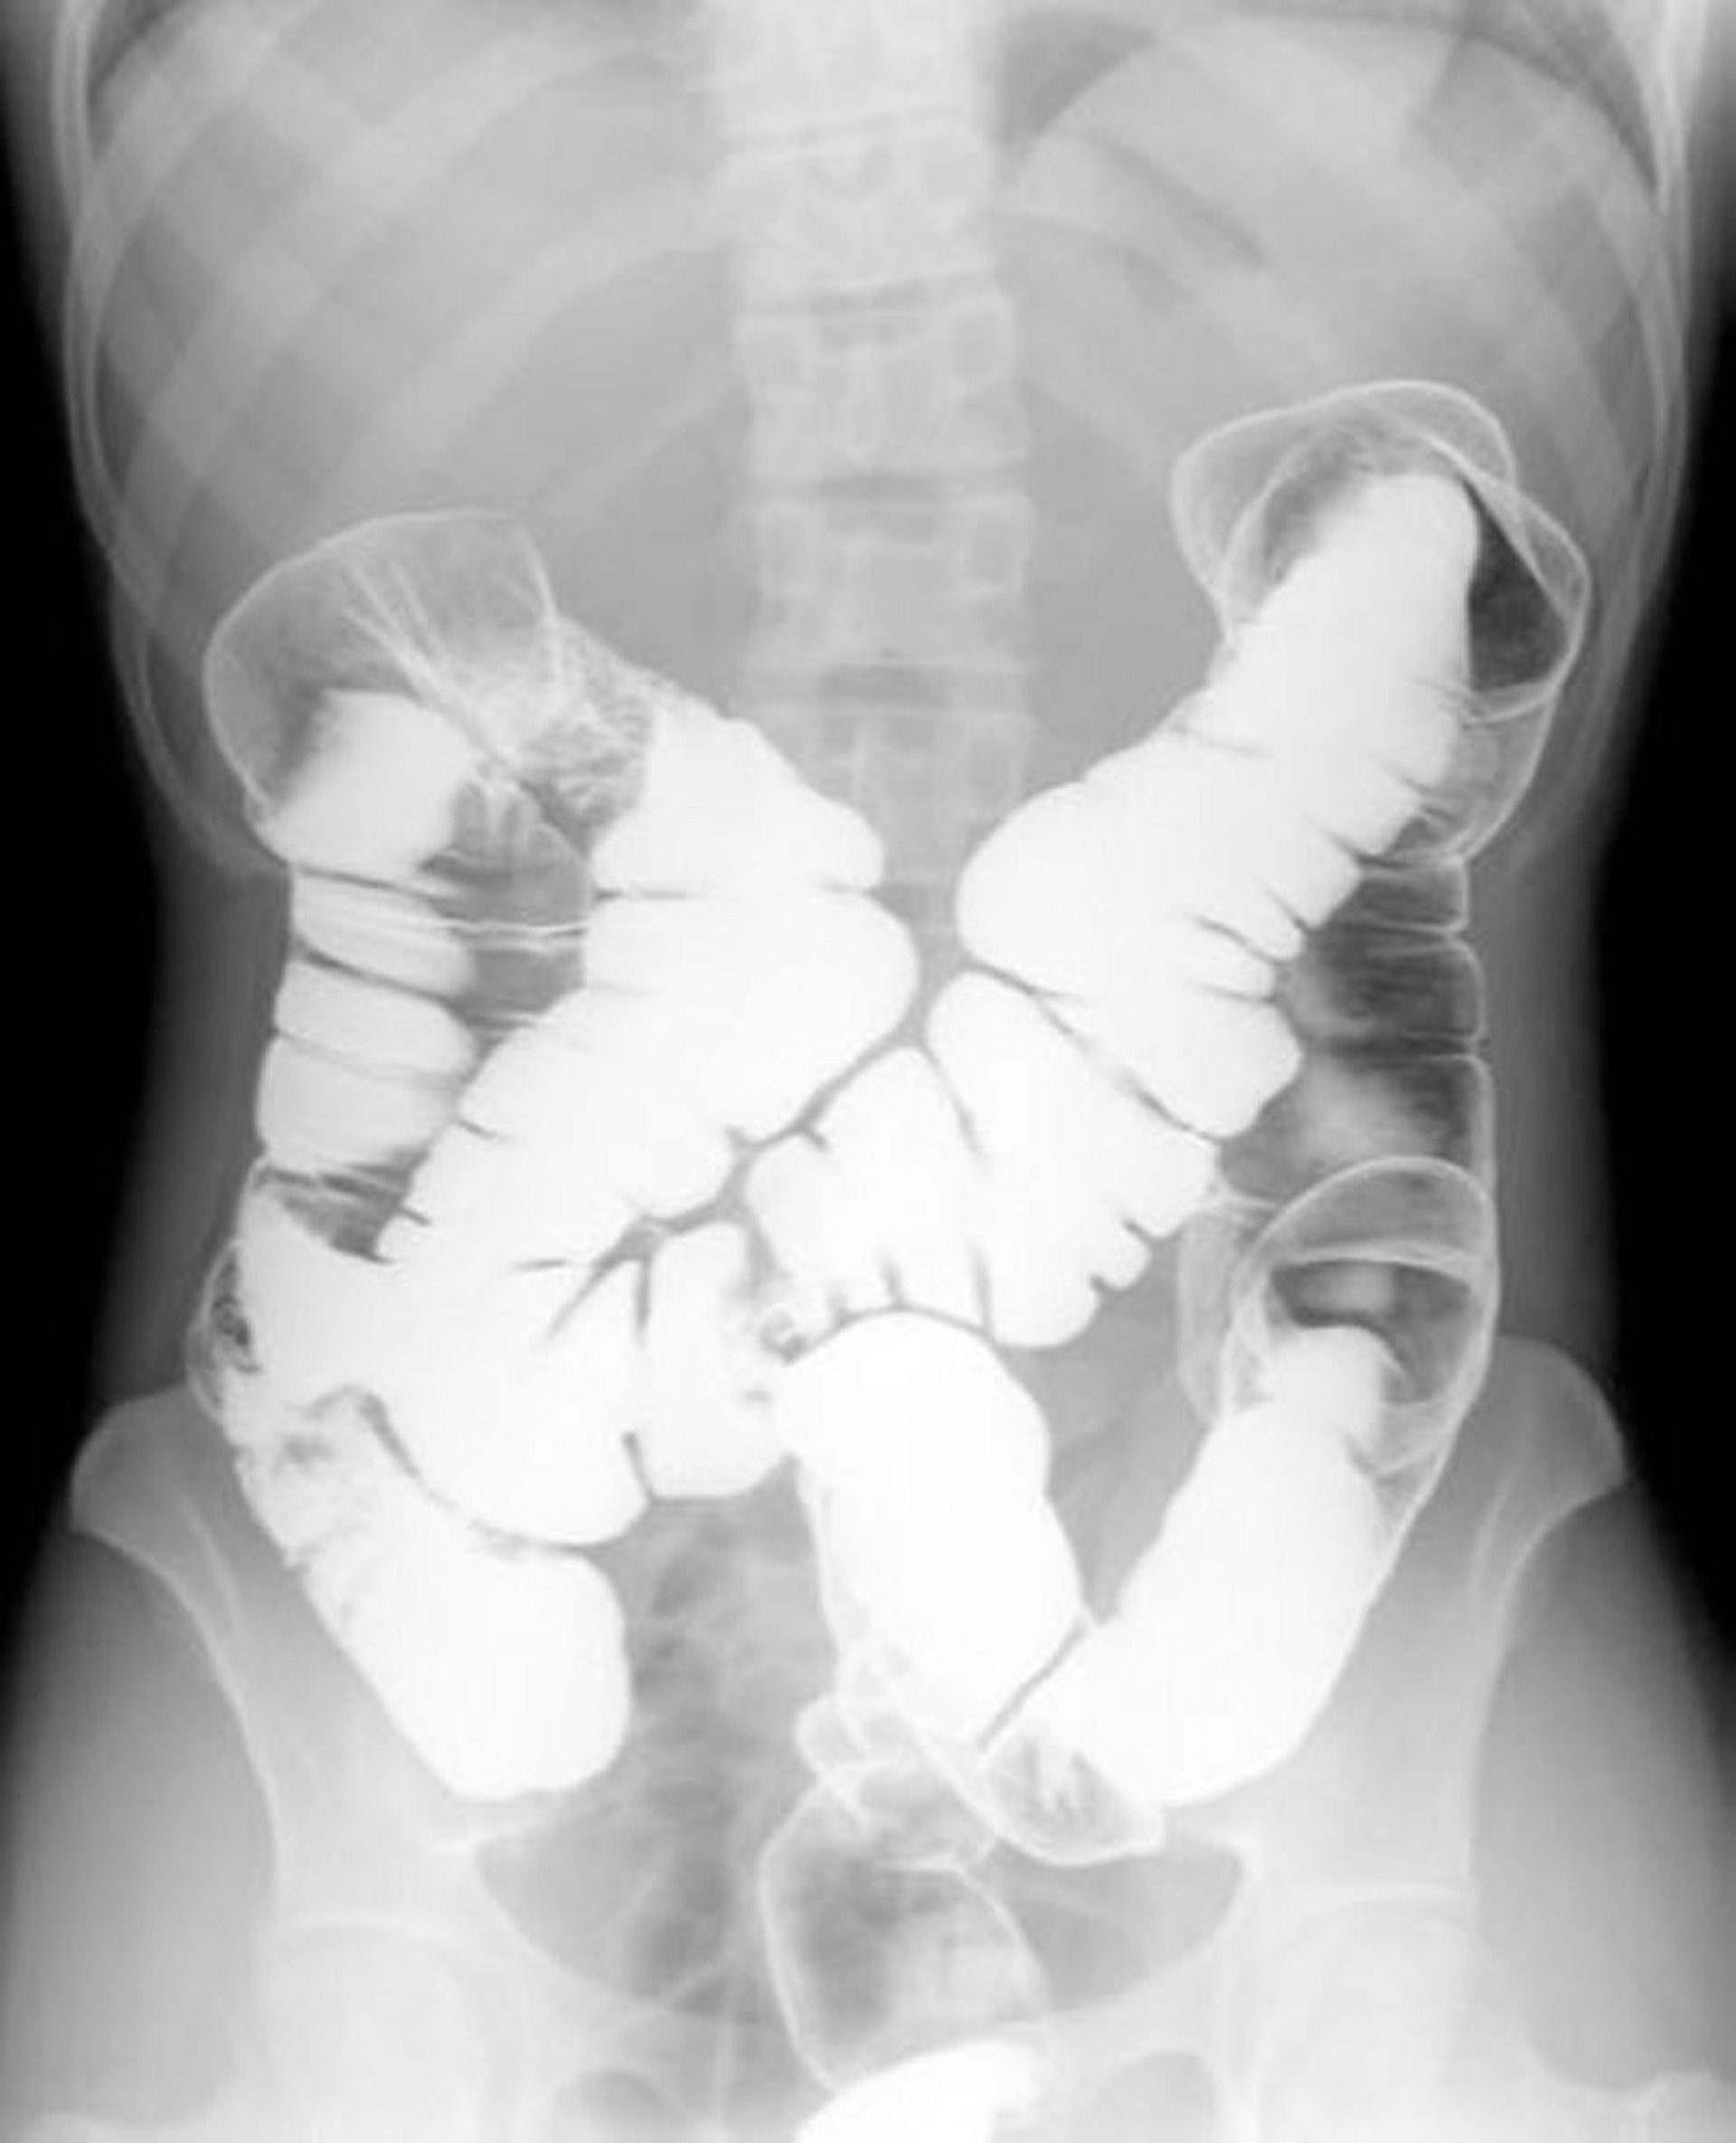

Doppelkontrast-Bariumeinlauf mit Darstellung der normalen Anatomie

Dieses Bild zeigt das Muster von Luft und Barium in einem normalen Kolon.